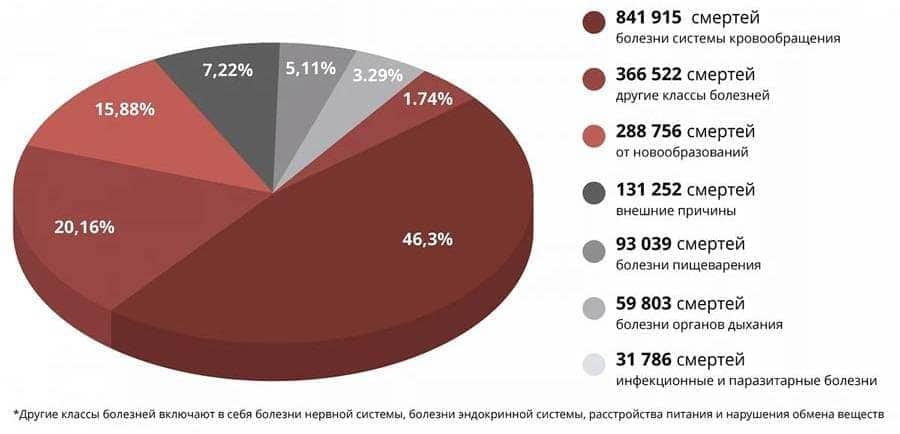

В нашей стране инсульты и инфаркты на фоне запущенной гипертонии рано

или поздно развиваются у 89% пациентов. Менее чем за 3-5 лет после

подтверждения диагноза большинство из гипертоников умирают. Ежегодно

гипертония уносит 82 тысячи наших граждан!

Статистика шокирует! Эпидемия забрала 25 тысяч жизней, а от проблем с сосудами и сердцем за это же время умерло почти 500 000 россиян.